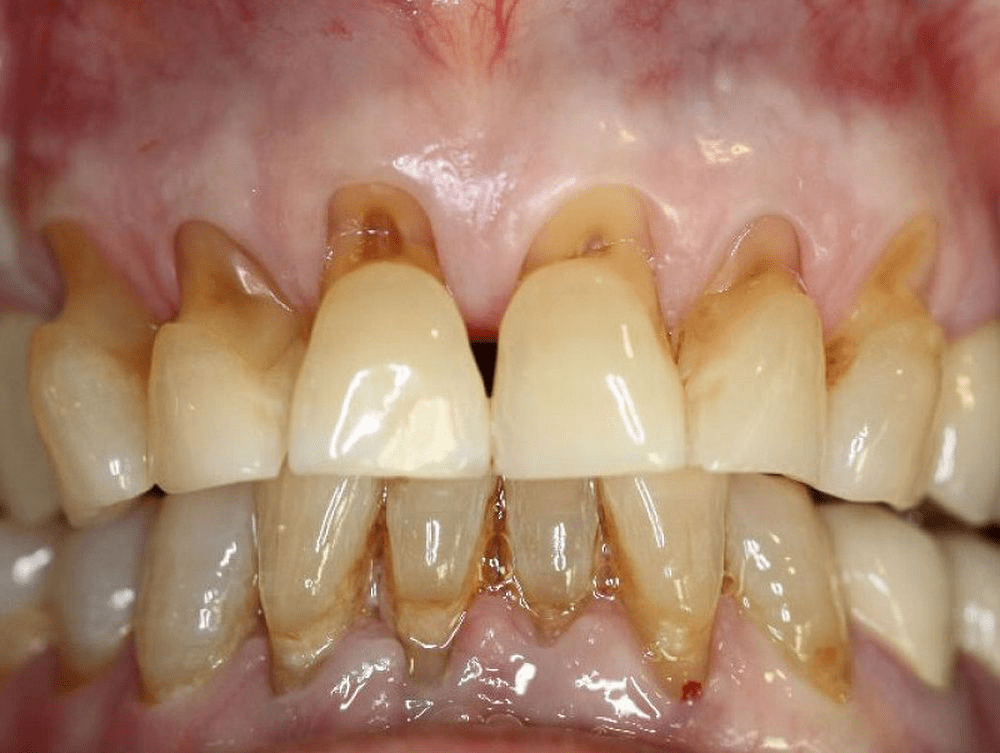

ABFRACTION lesions arises from clenching and is more common in the back (posterior) teeth and the canines but they can occur in the front (anterior) teeth as well. The characteristic appearance is of a straight line break parallel to the occlusal plane near the gumline and it causes the gums to recede. The straight line wedge breakage is a feature of the stress fracture of a hard tooth structure from the bending of the tooth when you gnash them together and move your jaw side to side. Studies have shown that when you do this in your sleep it can be up to 40 times stronger than you could do it when you are awake. You could not do it even if you tried when you are conscious as your higher brain will stop you from doing so. Bruxism is proportional to stress.

When the enamel has broken the dentine ( soft part of the tooth underneath the enamel) can erodes giving these lesion the appearance of acid erosion and toothbrush abrasion. You can of course get decay in these areas once broken as it can become a food trap. While it is possible to have the acid erosion, I do not believe toothbrush abrasion is a likely culprit. These are secondary to the main issue of the abfraction which is in fact the result of bruxism.

Long before the visible signs of abrasion are detected you will feel the sensitive teeth as an early warning that you are abfraction your teeth. Because abfraction is due to bruxism all the associated symptoms of bruxism should be use as an even earlier warning of the impending damage of abfraction. By the time you feel the sensitive teeth – usually cold – your teeth has already started to break even if you can see it yet. Remember the damage is irreversible. You can only hope to stop the progress by firstly being aware and secondarily using an occlusion splint at night when you sleep.

The lost of your canine prominence accelerates the abfraction of the posterior teeth. It is important to reestablish canine disclusion if you have worn down your canines or orthodontically establish it if your bite is not correct.